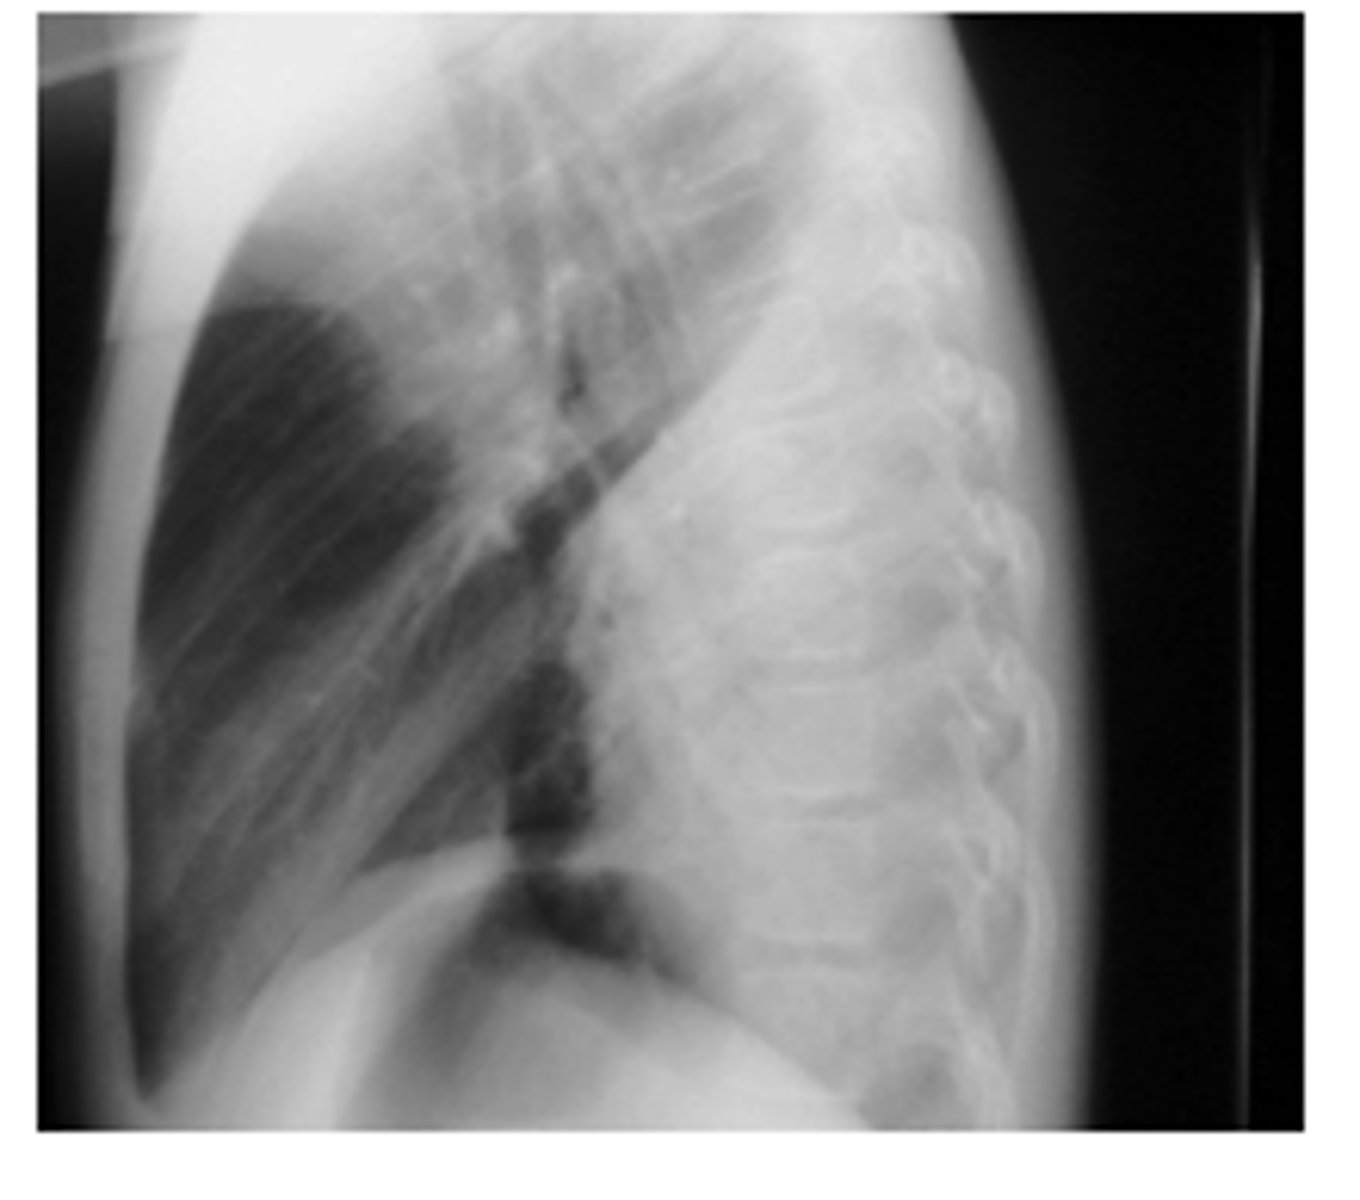

ID sign on back and finding

RML pneumonia obscuring the cardiac border but not the R hemidiaphragm. Note the triangular density on the lateral view.

<p>RML pneumonia obscuring the cardiac border but not the R hemidiaphragm. Note the triangular density on the lateral view.</p>